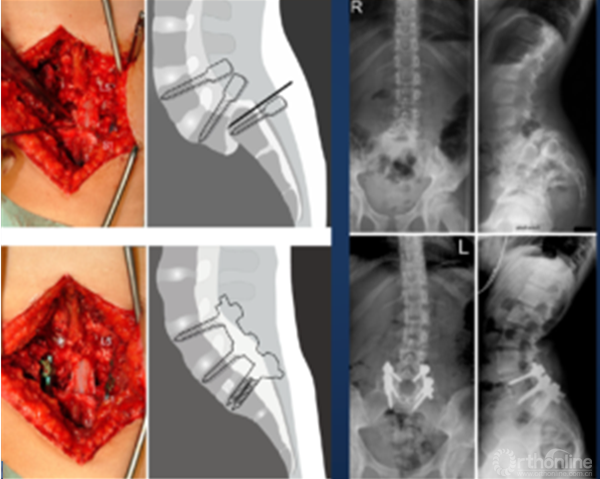

① 对于失平衡不重者,可以采取一期后路部分复位和经骶骨轴向融合方式[4]。

② 明显失平衡者,采取后路复位联合前路支撑重建术式。

2. 骶骨形态不规则

① 采取前后联合,骶骨部分截骨、复位和椎间支撑重建手术[8]。

② 我们的病例